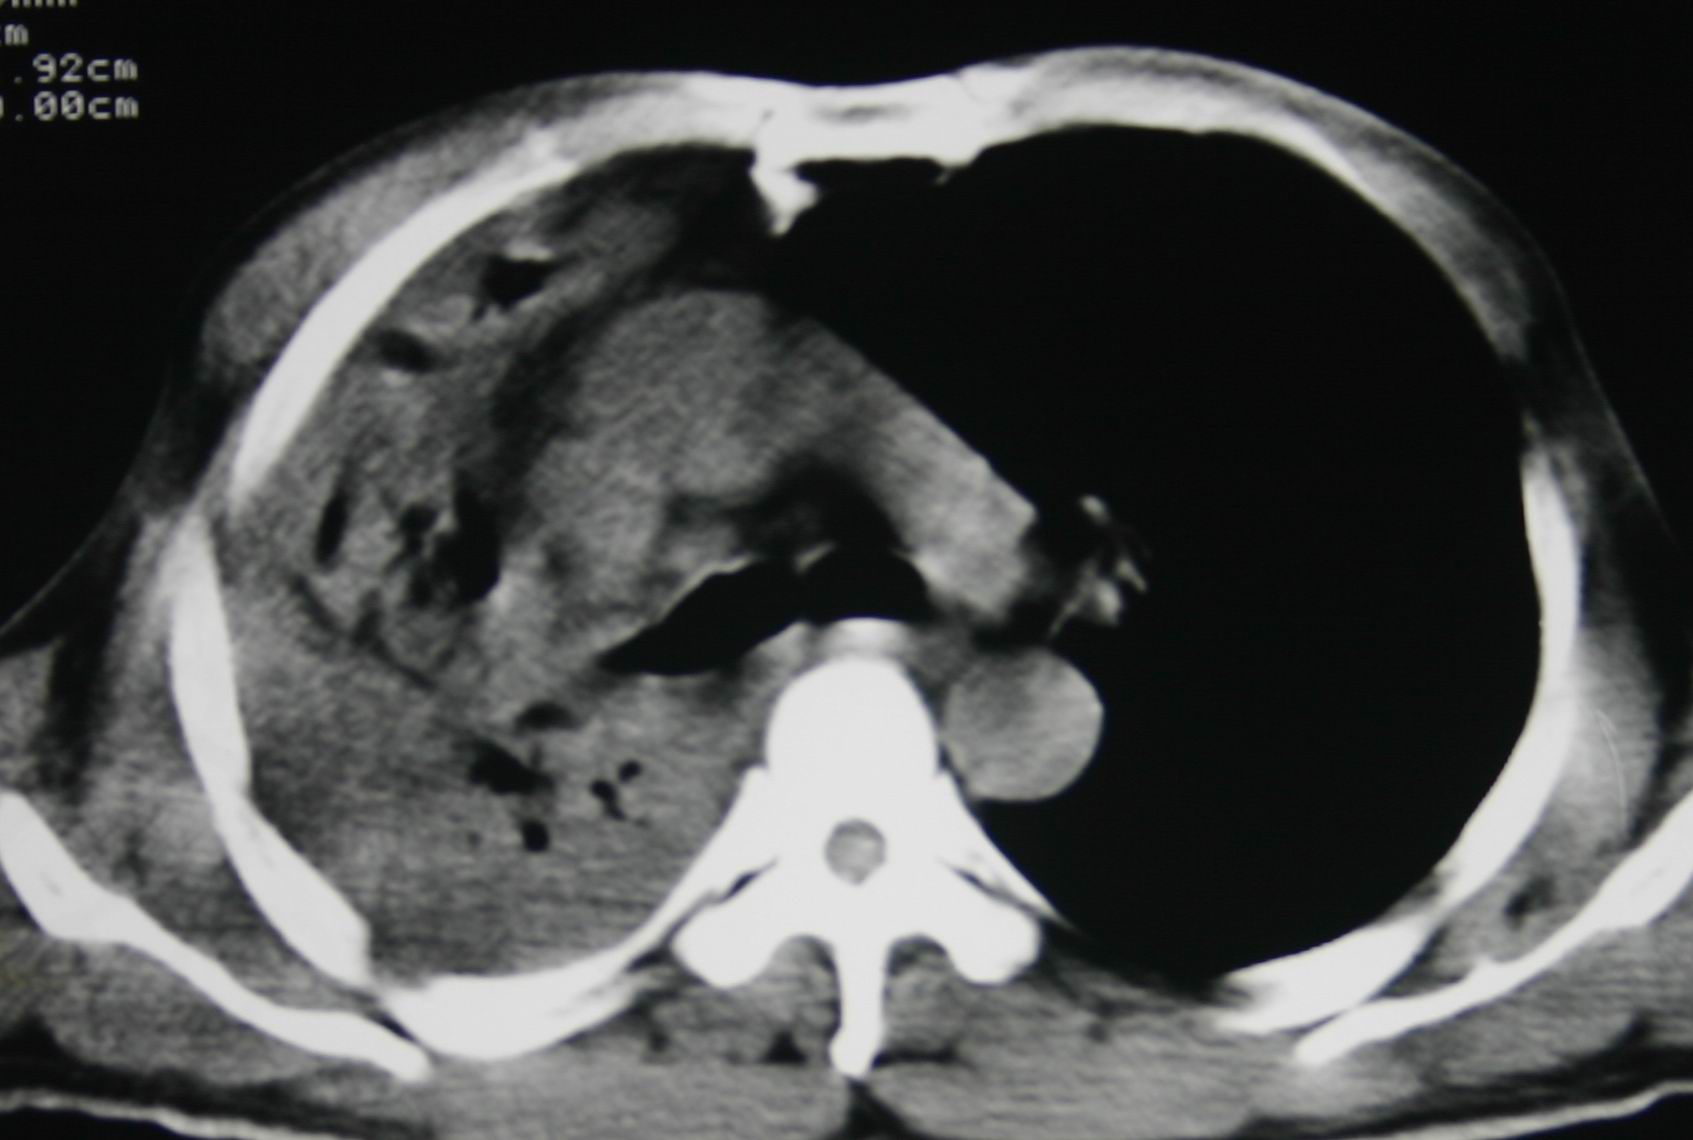

患者,男 ,48岁,反复咯血三个月,每三到五天咯一次,每次约200ml,鲜红色,无明显咳痰,咳嗽明显,无明显胸痛,无发烧,初期以抗感染、止血治疗,第一次ct报占位,支气管镜未见明显ca细,肺ca标志物、tb抗体均阴性,经过垂体后叶素、酚妥拉明、头胞他定、洛美沙星、立止血等治疗后,现病人一般情况好,停止咯血10天,咳嗽减少,咳黄脓痰,每日一次,每次30ml。现复查ct

右肺膨胀不全,纵隔右侧移位。肺内有感染,胸腔有积液。建议老片对比。

1)考虑右肺继发性肺结核合并感染。2)右侧胸腔积液+胸膜增厚。

支持:右肺膨胀不全,纵隔右侧移位。肺内有感染,胸腔有积液。建议老片对比。